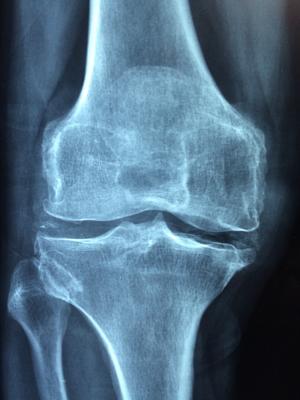

Osteoarthritis often occurs after a joint is injured, leading to progressive damage of the cartilage that lines and cushions the joint and causing pain and stiffness.

Today, joint pain often is assessed by X-ray or magnetic resonance imaging (MRI), which shows if the cartilage lining the joint has been damaged. In most cases, by the time a patient has pain, the damage to the joint is irreversible. The only permanent solution is to surgically replace that joint. Joint replacement is a common procedure: 719,000 knee replacements and 332,000 hip replacements are performed every year, according to the Centers for Disease and Prevention (CDC).